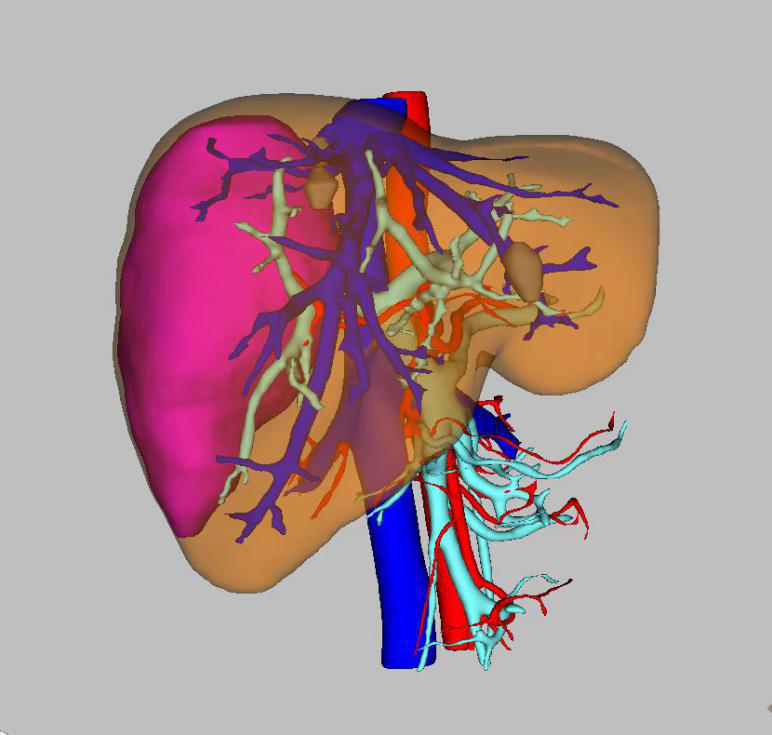

41岁的患者颜某,2月前在体检检查中发现肝占位性病变,但并未给予特殊治疗,近日患者右上腹部隐痛不适频繁发作,遂来我院就诊。行腹部增强CT检查后,诊断为肝血管瘤,肝胆胰外科陶锐主任医师组织团队谨慎地讨论了颜女士的病情,经三维可视化重建技术将肿瘤行重建后,最终决定以腹腔镜的形式切除血管瘤。

(图示中红色部分为肝血管瘤所在位置及体积)

手术由陶锐主任医师主刀,带领安代红副主任医师、张超超主治医师,及麻醉护理团队,经过3个多小时的紧密协作,顺利将颜女士体内的血管瘤切除。